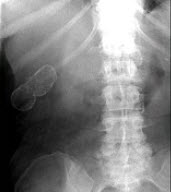

女,39岁,右上腹部隐痛,有慢性胆囊炎史,曾经做过口服胆囊造影,胆囊未正常显影,X线检查如图,最可能的诊断是( )

A:急性胆囊炎

B:慢性胆囊炎

C:胆囊结石

D:瓷样胆囊

E:胆囊结核